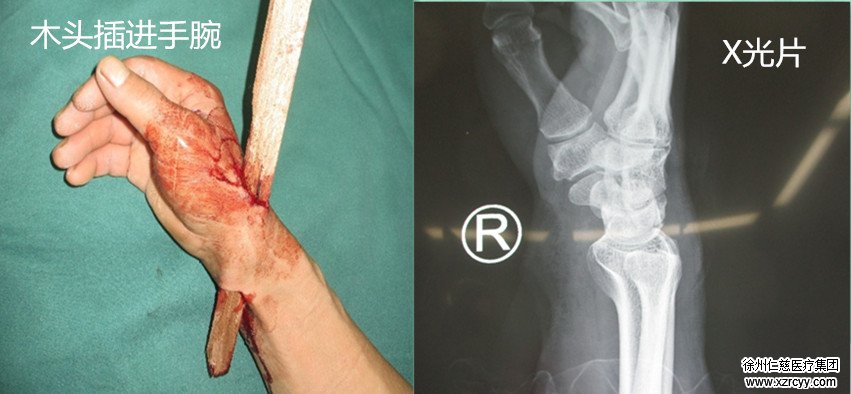

操作不慎木头横插手腕

1月8日上午,与往常一样,李师傅在厂里进行木材打磨工作。刚开始的几根并没有问题,可谁知,到第8根的时候,机器突然停顿没了动静。“我心想可能是卡住了,就用手捣了一下,谁知道卡的太紧,天冷木材又脆,就……”peng的一声,木条从三分之一处断裂,形成锋利的刺,巨大的贯穿力,瞬间将李师傅的右手腕刺穿。

“右腕远端桡背侧至腕部近端掌侧见一贯通伤口、内见活动性出血及木头残留、伤口创缘不齐。挫伤、污染较重。”经过初步的检查后,接诊的郑大伟主任当即决定“通知在办公室里值班的医生去手术室,紧急抢救”。

郑主任介绍“手术中我们发现,异物致使病人手腕部桡动脉及伴行静脉断裂,桡神经浅支断裂,肌腱断裂。”而且,与普通贯通伤口不同,因为木材质地的原因,伤口部位沾染了大量木材碎屑。如果不清理干净,很容易造成伤口感染。